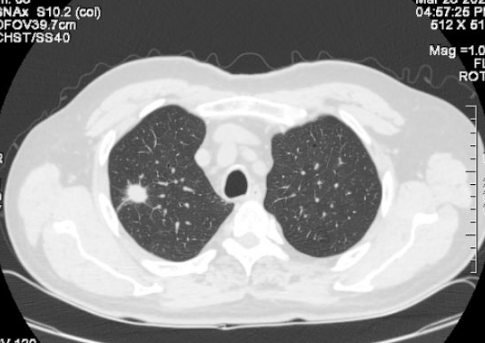

近年来,肺结节的发病率越来越高。我们经常可以看到或听到身边的亲友,体检时发现肺结节。造成这种情况的原因,一方面是现代人生活节奏快、工作压力大、生活习惯差、空气污染等,导致肺结节的发病率较以前有所增加。另一个方面是,过去在例行体检中,通过胸部X光片来确定肺部的状况。

但是X线对软组织的分辨率不是很高,小于一厘米的结节很难发现。现在,越来越多的人在体检时选择胸部CT检查。这样,随着医学影像诊断技术的进步,两到三毫米的肺结节也能被发现和检测到。因此,总的来说,肺结节的发现率越来越高。